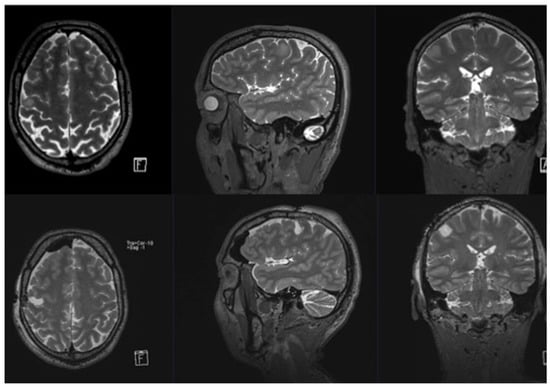

3.1. Patient Population

3.2. Intraoperative Findings

3.3. Clinical Findings